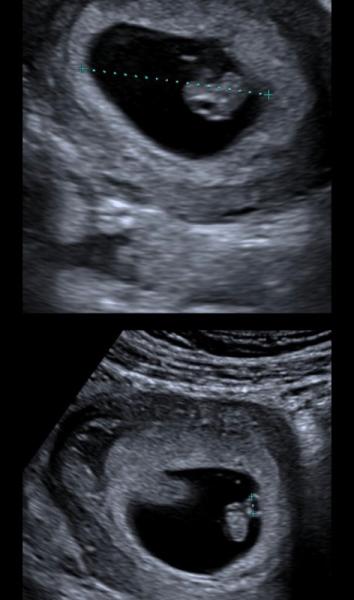

So spannend. Ich würde auch gerne mal wissen was Ihr denkt was es bei mir wird. Links ist von der 6 ssw Und jetzt jetzt 8 ssw. Würde mich über eine Antwort freuen:)

Wenn der Ultraschall vaginal gemacht wurde, würde es laut Ramzi Methode ein Mädchen sein ![]() Wenn es über den Bauch gemacht wurde also spiegelverkehrt dann ein Junge

Wenn es über den Bauch gemacht wurde also spiegelverkehrt dann ein Junge ![]()